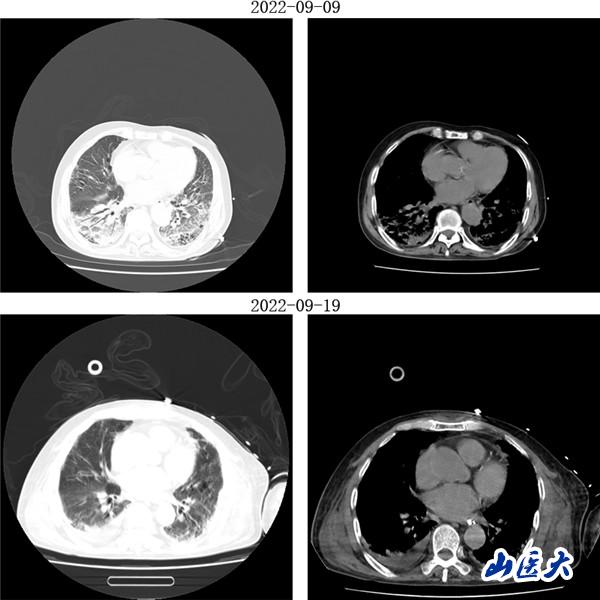

重症医学科三病区张文凯主任团队深入分析了两位患者的病情。考虑到两名老年患者均已出现急性呼吸窘迫综合征,决定采用俯卧位通气技术为他们治疗。在张文凯主任的指导下,侯林义主治医师带领张承、孙洁住院医师对女性患者经俯卧位通气治疗,92小时后复查胸部CT,双肺明显好转,氧合指数由90上升至300mmHg以上,吸氧浓度由100%降至35%,ARDS明显改善;对男性患者,采用联合持续性血液滤过(CRRT)治疗方案,经俯卧位通气治疗66小时后复查胸部CT,显示明显改善,同时氧合指数由102上升至360mmHg左右,吸氧浓度需求下降至40%,全身水肿情况也明显减退。

(男性患者治疗前后胸部CT对比)